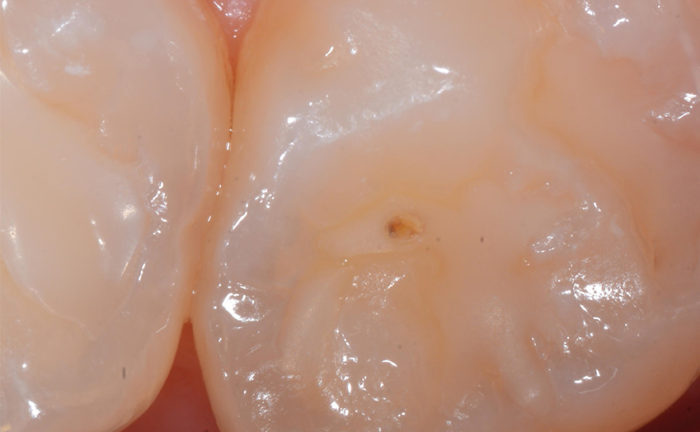

Die Blase in einer Fissurenversiegelung (Kavität der Klasse I) ist ein allzu häufiger Anblick).